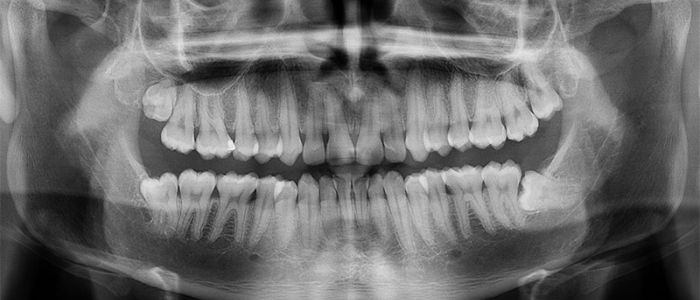

Las radiografías extraorales se emplean cuando no es factible obtener información diagnóstica adecuada en las series de radiografías intraorales, es así que son utilizadas para observar un área grande de los maxilares y del cráneo en una sola radiografía. Los exámenes radiográficos extrabucales tienen el propósito de evaluar áreas grandes del cráneo, dientes impactados y patrones de erupción, crecimiento y desarrollo; examinar la extensión de lesiones grandes, traumatismos, articulación temporomandibular. Son de mucha utilidad principalmente en Ortodoncia y Cirugía Bucal.

Existen varias radiografías extraorales entre las cuales se tiene: